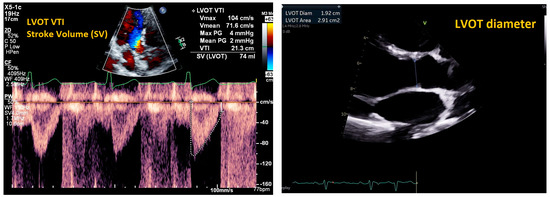

| Mitral E/e’ ratio estimated from the E wave velocity of the mitral inflow Doppler envelope and the tissue Doppler e’ wave velocity at the mitral annulus (septal and/or lateral) | E/e’ ≤ 14 |

|

| |

| DT in the mitral inflow Doppler envelope | 160–200 ms |

| Peak velocity of the TR jet | ≤2/8 m/s |

| Estimated PASP using TR jet plus estimated RAP from IVC assessment | ≤35 mmHg |